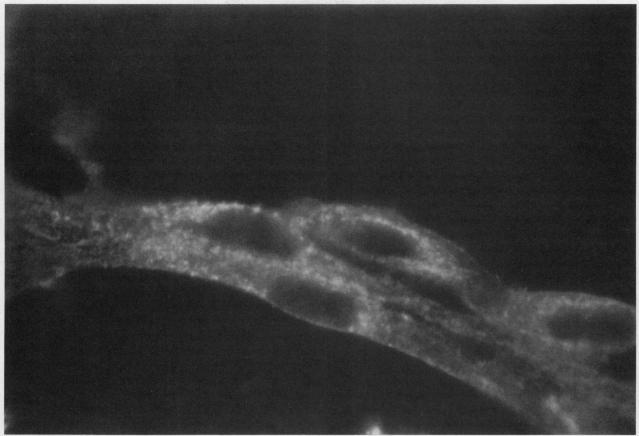

Studies of bone marrow transplant patients have suggested that the stromal cells of the in vitro hematopoietic microenvironment are transplantable into conditioned recipients. Moreover, in patients with myeloproliferative disorders, all of the stromal cells, which include presumptive endothelial cells, appear to be derived from hematopoietic precursors. To confirm these findings, we have constructed two chimeric mouse models: (a) traditional radiation chimeras, and (b) fetal chimeras, produced by placental injection of bone marrow into genetically anemic Wx/Wv fetuses, a technique that essentially precludes engraftment of nonhematopoietic cells. Using two-color indirect immunofluorescence, the stromal cells in long-term bone marrow culture derived from these chimeras were analyzed for donor or host origin by strain-specific H-2 antigens, and for cell lineage by a variety of other specific markers. 75-95% of the stromal cells were shown to be hematopoietic cells of the monocyte-macrophage lineage, based upon donor origin, phagocytosis, and expression of specific hematopoietic surface antigens. The remaining 5-25% of the stromal cells were exclusively host in origin. Apart from occasional fat cells, these cells uniformly expressed collagen type IV, laminin, and a surface antigen associated with endothelial cells. Since these endothelial-like cells are not transplantable into radiation or fetal chimeras, they are not derived from hematopoietic stem cells. The contrast between our findings and human studies suggests either unexpected species differences in the origin of stromal lineages or limitations in the previous methodology used to detect nonhematopoietic stromal cells.

对骨髓移植患者的研究表明,体外造血微环境的基质细胞可移植到经过预处理的受体体内。此外,在骨髓增殖性疾病患者中,所有的基质细胞,包括推定的内皮细胞,似乎都来源于造血前体细胞。为了证实这些发现,我们构建了两种嵌合小鼠模型:(a) 传统的辐射嵌合体,以及 (b) 通过将骨髓经胎盘注射到遗传性贫血的Wx/Wv胎儿中产生的胎儿嵌合体,该技术基本上排除了非造血细胞的植入。使用双色间接免疫荧光法,通过菌株特异性H-2抗原分析这些嵌合体来源的长期骨髓培养物中的基质细胞的供体或宿主来源,并通过多种其他特异性标志物分析细胞谱系。基于供体来源、吞噬作用和特异性造血表面抗原的表达,75-95% 的基质细胞被证明是单核细胞-巨噬细胞谱系的造血细胞。其余5-25% 的基质细胞完全来源于宿主。除了偶尔的脂肪细胞外,这些细胞均一表达IV型胶原、层粘连蛋白以及一种与内皮细胞相关的表面抗原。由于这些内皮样细胞不能移植到辐射或胎儿嵌合体中,它们并非来源于造血干细胞。我们的研究结果与人体研究之间的差异表明,基质谱系起源存在意想不到的物种差异,或者先前用于检测非造血基质细胞的方法存在局限性。